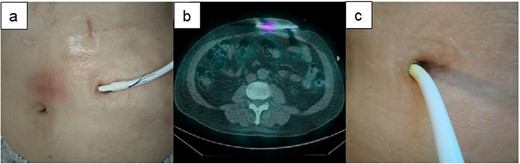

A 43-y-old man with ischemic cardiomyopathy underwent LVAD implantation (HeartMate II™, Abbott Co., Abbott Park, IL, USA) and was readmitted to our hospital because of DLI 3.5 y after this implantation. The DLES had erythema and induration with purulent discharge (Fig. 4a). Culture of the DLES had previously shown the presence of methicillin-resistant Staphylococcus aureus (MRSA). The patient was admitted to our hospital for surgical relocation of the DLES for deep DLI. However, as 67Ga SPECT showed an inflammation area localized 5 cm around the DLES (Fig. 4b), the catheter cleaning method was firstly selected prior to a surgical approach. Appropriate intravenous antibiotic therapy was administered for about 6 weeks, and debridement and cleaning of the infected area via the DLES were performed daily for about 2 months. The catheter cleaning method via the DLES was effective for his DLI; the local increase in temperature gradually improved, and exudation decreased (Fig. 4c). The patient was discharged on day 66 after hospitalization. Oral antibiotic therapy was continued after discharge and was completed after approximately 3 months. DLI has not reoccurred in the 6 months after discharge.

The clinical course of recurrence of the DLI in Case 2. (a) The DLES had erythema and induration. (b) 67Ga SPECT showed an inflammation area localized to 5 cm around the DLES. (c) Purulent discharge was decreased, and the space around the driveline was reduced.